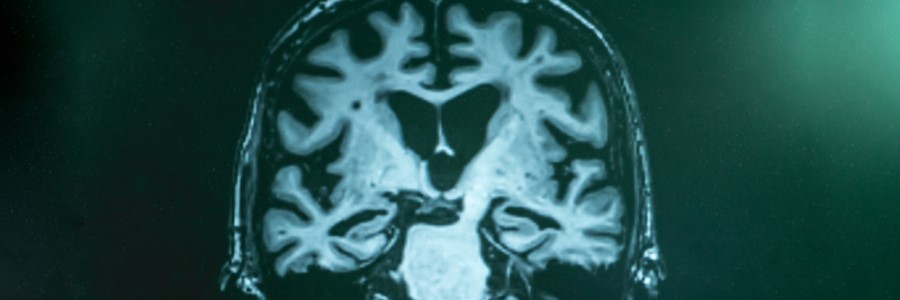

La presenilina es una proteína que está relacionada con el desarrollo de la enfermedad de Alzheimer. Y es que algunos estudios han descubierto que cuando esta se encuentra en bajas concentraciones o disminuyen sus funciones, empiezan a aparecer problemas de memoria y un deterioro cognitivo que puede agravarse con el paso del tiempo.

Esta proteína puede presentar mutaciones en los genes PS1 y PS2. No obstante, estas también se pueden manifestar —aunque de una manera mucho menos habitual— en la proteína beta-amiloide. Esta última tiene una gran importancia, ya que cuando se acumula en el cerebro se empieza a producir, de manera progresiva, un deterioro de la función cognitiva que puede acabar derivando en la enfermedad de Alzheimer.

A pesar de la relación que tiene la presenilina con esta enfermedad, en realidad su presencia es importante para el buen funcionamiento de determinados procesos. Por ejemplo, el desarrollo neuronal de un bebé durante la gestación. Por lo tanto, es necesaria, aunque también puede vincularse con el Alzheimer, una enfermedad que en la actualidad afecta a unas 800.000 personas solo en España, según datos de la SEN.